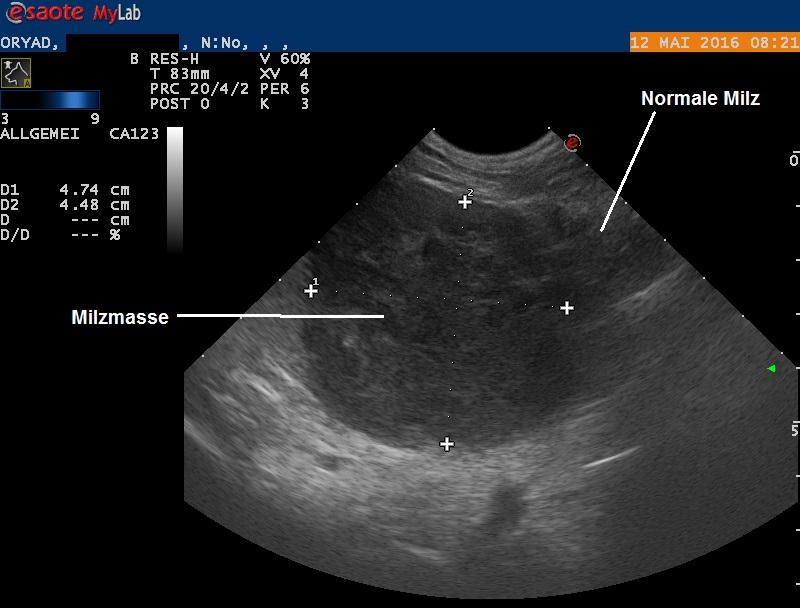

Obwohl nun bekannt ist, dass sich im Bauch des Hundes ein Knoten verbirgt und dieser zielgerichtet abgetastet werden kann, erweist sich die Masse als nicht ertastbar. Im Ultraschall findet sich dann aber ein knapp 5 cm messender, kugeliger Knoten innerhalb der Milz. Der Knoten zeigt eine heterogene (uneinheitliche) Echotextur und enthält auch kleine Hohlräume, welche mit Flüssigkeit gefüllt scheinen. In der Bauchhöhle findet sich aber keine Flüssigkeit, die restlichen Bauchorgane erscheinen unauffällig, und auch ein kurzer Ultraschall des Herzens verläuft unauffällig.

Da davon ausgegangen werden muss, dass der Milzknoten für den verschlechterten Allgemeinzustand von Oryad verantwortlich ist, wird der Entscheid zur Entfernung der Milz gefasst. Eine vorgängige Gewebeprobe mittels Feinnadelaspiration wird nicht durchgeführt, da bei zwei der möglichen Geschwulsttypen (Hämangiosarkom sowie Bluterguss, siehe Fall 19 ) eine Gewebediagnose sehr schwierig ist und mit einem starken Blutungsrisiko verbunden ist.